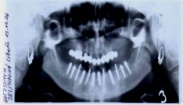

• Dokonalé vyšetření, stanovení diagnózy,naplánování ošetření - způsob, časový průběh,cena

• Zavedení implantátu do kosti čelisti

• Zahojení do kosti – 3-4měsíce(v některých případech i déle – doplňování kosti)

Zavedení implantátů do kosti je většinou ambulantní chirurgický výkon, srovnatelný s vytržením zubu a většinou se provádí v lokální anestézii. Ve výjimečných případech je možné použít i analgosedaci či celkovou narkózu. Operaci provádí zubní lékař-implantolog při dodržení všech podmínek sterility pro operaci. Nástroje pro tuto operaci jsou konstruovány tak, aby výkon byl šetrný vůči kosti a zavedení implantátu bylo provedeno ve velmi krátké době. Díky kvalitní anestézii je výkon nebolestivý. Aby byl pooperační otok co nejmenší, je potřeba operovanou oblast chladit, dle poučení ošetřujícího lékaře. Lékař také ordinuje podle potřeby léky na bolest, případně antibiotika.

Průměrná doba hojení implantátů před provedením definitivního protetického ošetření je 3-4 měsíce, v případech, kde je nutné doplnit chybějící kost (různé metody, postupy a materiály) – tzv. augmentace) se může doba hojení prodloužit na 8-12 měsíců. S tím je pacient vždy předem seznámen svým lékařem.